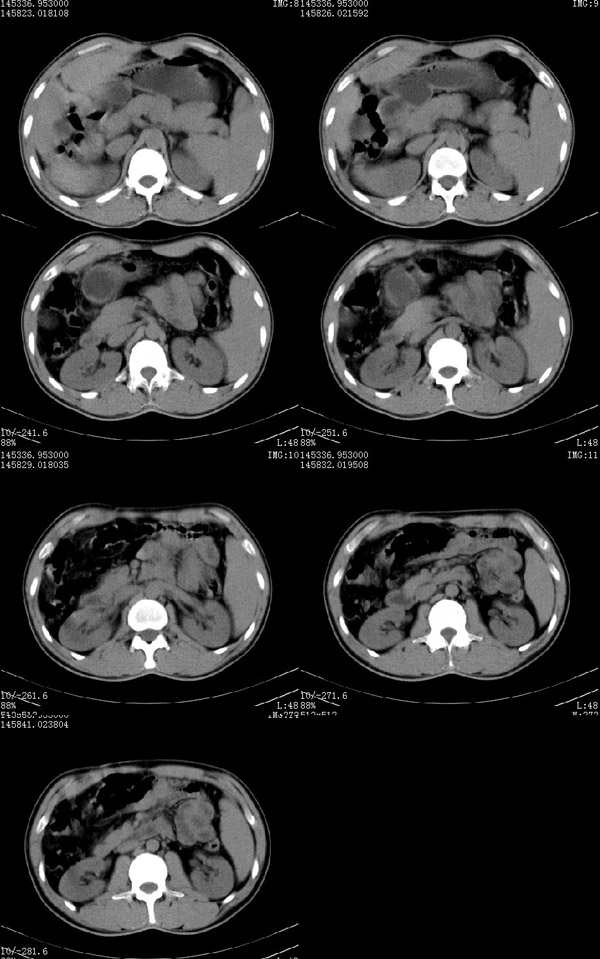

标题: CT4408:(续)肝癌术后CT表现

肝癌术后3个月(该患者硕士研究生,在四川开了一个宾馆.于做ct后第三天便在四军大西京医院做了手术,手术顺利.病人恢复良好.病理结果:肝细胞癌.最后诊断:原发性肝癌.)

10mm层厚扫描: